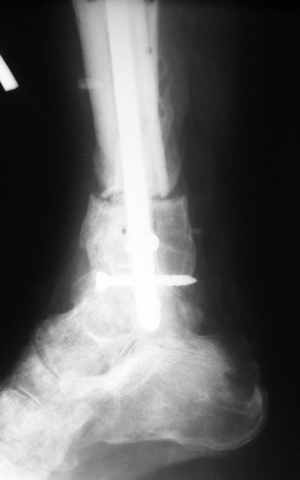

|  |  |  |  status localis на 14.11.08 (В ране визуализируется сухожилие.) | Больной А, 40 лет, находится в клинике с 15.10.08 с диагнозом: Сочетанная травма. Ушиб головного мозга лёгкой степени тяжести. Компрессионные переломы тел 12 грудного и 5 поясничного позвонков без неврологических осложнений. Закрытый внутрисуставной многооскольчатый перелом дистальных метаэпифизов обеих костей правой голени со смещением. Открытый внутрисуставной многооскольчатый перелом дистальных метаэпифизов обеих костей левой голени со смещением (см. Р-граммы). Хронический алкоголизм. Доставлен СМП после падения с 5-го этажа (не суицид). При поступлении состояние тяжелое. Глубокое оглушение. Дыхание самостоятельное, адекватное. Гемодинамика стабильная. По внутренней поверхности левой голени, в нижней трети, рвано-ушибленная рана 10-6 см, из раны выстоит проксимальный отломок большеберцовой кости, рана обильно загрязнена землёй. Интенсивная терапия в условиях реанимационного отделения, вытяжение за правую пяточную кость, параартериальная блокада обеих нижних конечностей, гипсовая лонгета на левую нижнюю конечность, ас-повязка на рану. Через 4 часа после поступления оперирован: после неоднократного промывания раны тёплой проточной водой с мылом, антисептиками, при ревизии определяется земля в канале проксимального отломка на глубину 3 см..., отсутствие надкостницы на концах дистального и проксимального отломков на 3 см. Удалено значительное количество мелких костных фрагментов, перемешанных с землёй, выполнена ПХО раны, резекция проксимального конца большеберцовой кости на 3,5 см, ЧКДО аппаратом Илизарова. Рана не ушивалась. В последующем перевязки раны с "Левомеколь", через 3 недели с момента травмы в ране определялись грануляции, нежизнеспособный конец дистального отломка. 10.11.08 ВХО раны, резекция дистального отломка на 3 см, перемонтаж аппарата наружной фиксации (см. Р-граммы). Отломки сближены на 2 см (остеотомию малоберцовой не делали). В настоящее время (5 сутки после операции) незначительное количество серозного отделяемого из раны, имеется дефект кости 4 см (см. Р-граммы). В последующем склоняемся к перемонтажу аппарата наружной фиксации, остеотомии малоберцовой кости в области повреждения, сближении отломков. По заживлению раны удлинение левой голени на 4 см. Однако, некоторыми высказывалось мнение о необходимости артродеза. Представляем рентгенограммы левой голени при поступлении, после повторного оперативного лечения и фото st.localis на 14.11.08. Будем очень благодарны за критику, комментарии, пожелания и мнения о дальнейшей тактике лечения.

В случае гладкого заживления раны, при условии положительного решения вопроса с металлом, планируем перемонтаж аппарата Илизарова, дополнительную резекцию дистального отломка, выведение полокости голеностопного сустава в правильное положение (см. боковую Р-грамму), одномоментно остеотомия большеберцовой кости. После восстановления длинны голени, по всей видимости, артродез голеностопного сустава.

Мы обычно не фиксируем малоберцовую кость. Просто стараемся сопоставить ее концы за счет хорошей репозиции. В представленном случае имеется некоторое смещение дистальных фрагментов кнаружи, и, как мне кажется, ротация их вместе со стопой кнутри (ротация хорошо заметна на прямом снимке по форме таранной кости и на боковом по соотношению отломков малоберцовой). Если это действительно так, то это несложно сейчас постепенно устранить в аппарате. И тогда концы малоберцовой кости будут находиться поближе друг к другу.